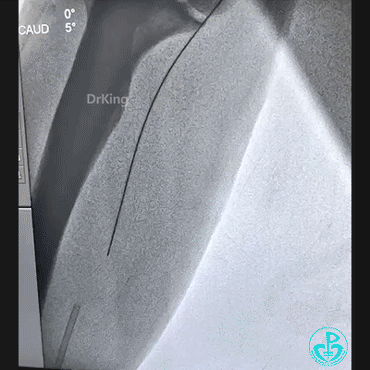

持续球囊锚定导丝调整指引导管角度,对准后回拉球囊,将导丝带入指引导管内,最后连同指引导管一起成功拉出。